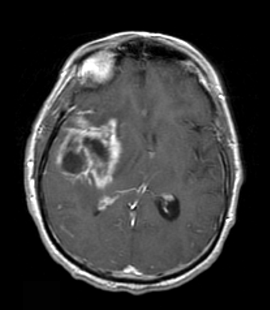

Pseudoprogression—MRI of a patient with a glioblastoma at 6 weeks post-chemoradiation demonstrating an initial increase in enhancement mimicking progressive disease.